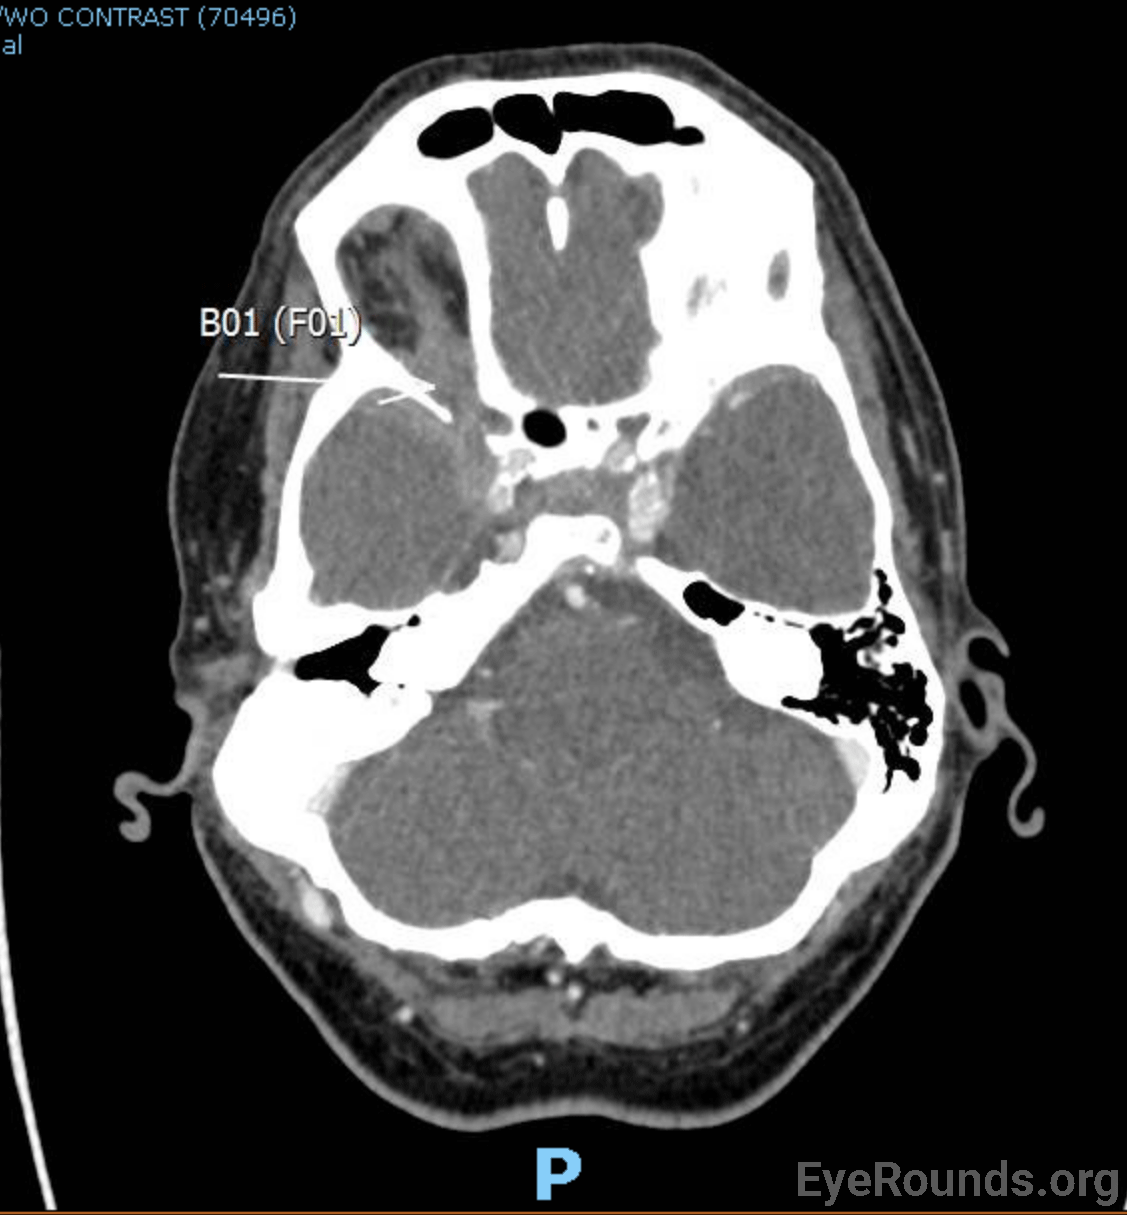

• CT Angiography Head with and without contrast (Figure 1 [A]): skull base metastatic disease with suspicion for tumor infiltration into the right superior orbital fissure

Figure 1: CT [A] and MRI [B] demonstrating lesions near the right superior orbital fissure. MRI also revealed leptomeningeal spread of disease and suspicion for right cavernous sinus thrombosis (not shown). Follow-up MRV (not shown) confirmed right cavernous sinus thrombosis.

CT scan on admission (Figure 1[A]) showed concern for a possible metastatic lesion involving the right superior orbital fissure. Due to concerns of a prior ear prosthesis placed following a stapedectomy over three decades ago with unknown MRI compatibility, MRI was delayed, and the patient was started on empiric dexamethasone of 4 mg twice daily. MRI was eventually performed which revealed a metastatic lesion involving the superior orbital fissure, thus confirming the diagnosis of superior orbital fissure syndrome on the right. There were also concerns for right cavernous sinus thrombosis, which was subsequently confirmed on MRV. The patient was not a surgical candidate and was treated with radiation therapy to the superior orbital fissure lesion. He was started on Apixaban 5 mg twice daily for treatment of the cavernous sinus thrombosis. The patient was noted to be hyponatremic during hospitalization and workup was consistent with syndrome of inappropriate antidiuretic hormone section (SIADH) which was responsive to fluid restriction. Dexamethasone was decreased to 2 mg twice daily at time of discharge, and he was noted to have minimal improvement in his ophthalmoplegia and ptosis 1 month after discharge.